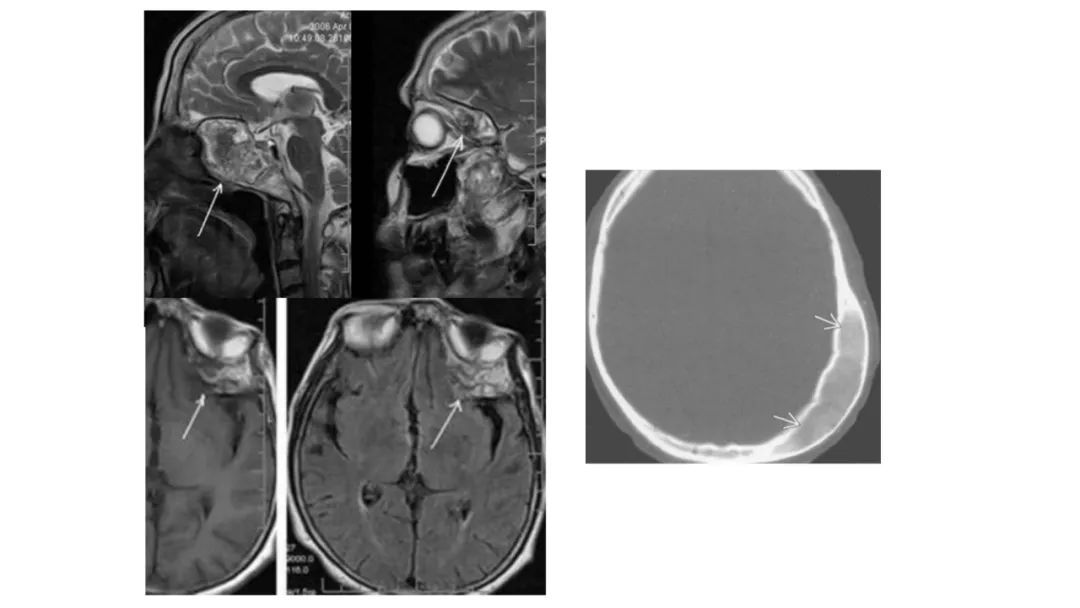

颅脑影像诊断基础知识讲座:颅骨病变